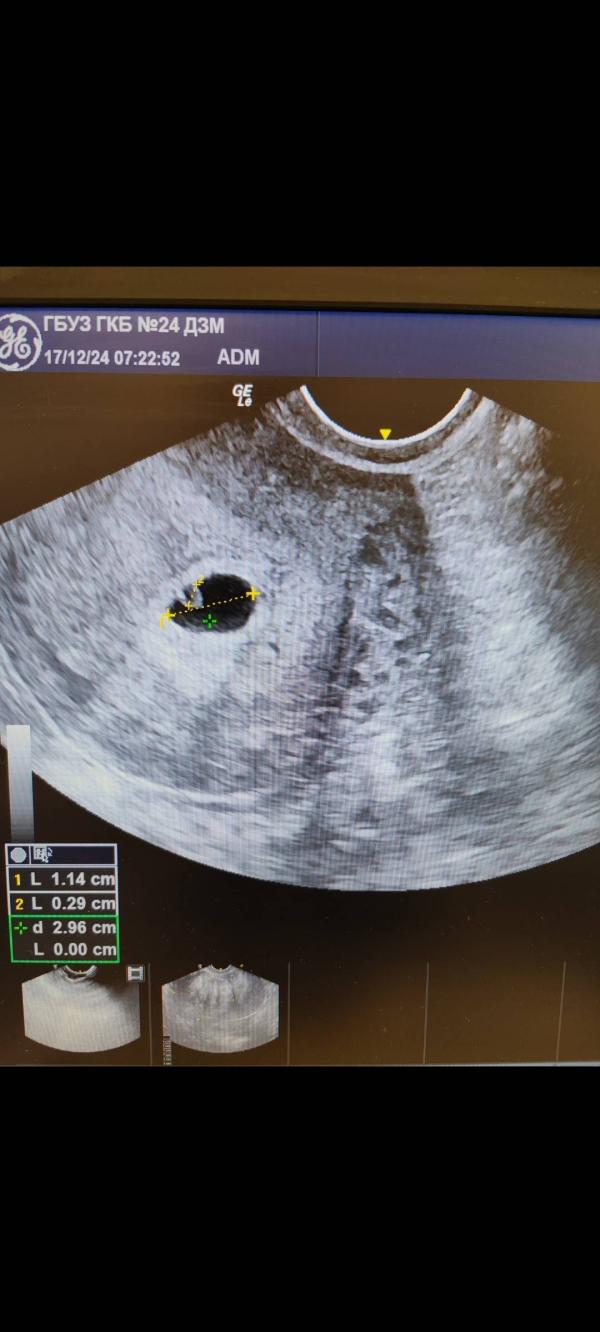

13 января на узи плоду поставили расширенное твп под вопросом, прослеживалась аномалия, но аппарат был не очень хороший, плохо было видно. Уже потом стало ясно, что это прогрессировала водянка, начал появляться отек.

А тут уже настоящий человек. Был. 17 января узи, в первые же секунды увидела, что пульсации нет. Водянка, очень отекший.. Генетика, без шансов.

Врач посоветовала съездить на еще одно узи. Все подтвердили слово в слово.